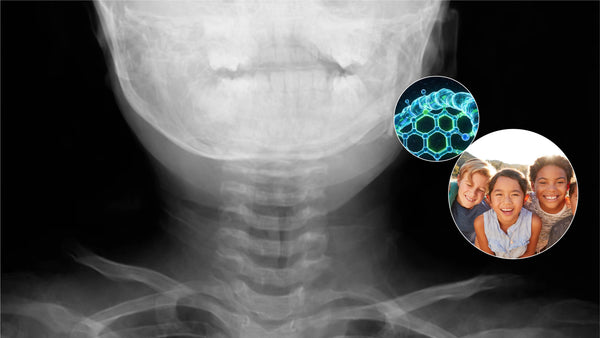

- The "Steeple Sign": In medical imaging, a neck X-ray of a child with croup often reveals a Steeple Sign. This is a visible narrowing of the trachea that looks like a church steeple, visually confirming the diagnosis.